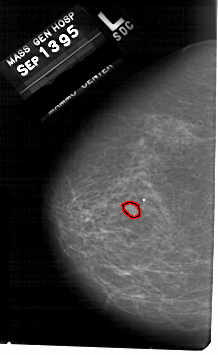

A_1676_1.LEFT_CC

LEFT_CC LINES 5311 PIXELS_PER_LINE 3256 BITS_PER_PIXEL 12 RESOLUTION 43.5 OVERLAY

FILE: A_1676_1.LEFT_CC.OVERLAY

TOTAL_ABNORMALITIES 1

ABNORMALITY 1

LESION_TYPE MASS SHAPE OVAL MARGINS OBSCURED

ASSESSMENT 4

SUBTLETY 3

PATHOLOGY MALIGNANT

TOTAL_OUTLINES 1

BOUNDARY